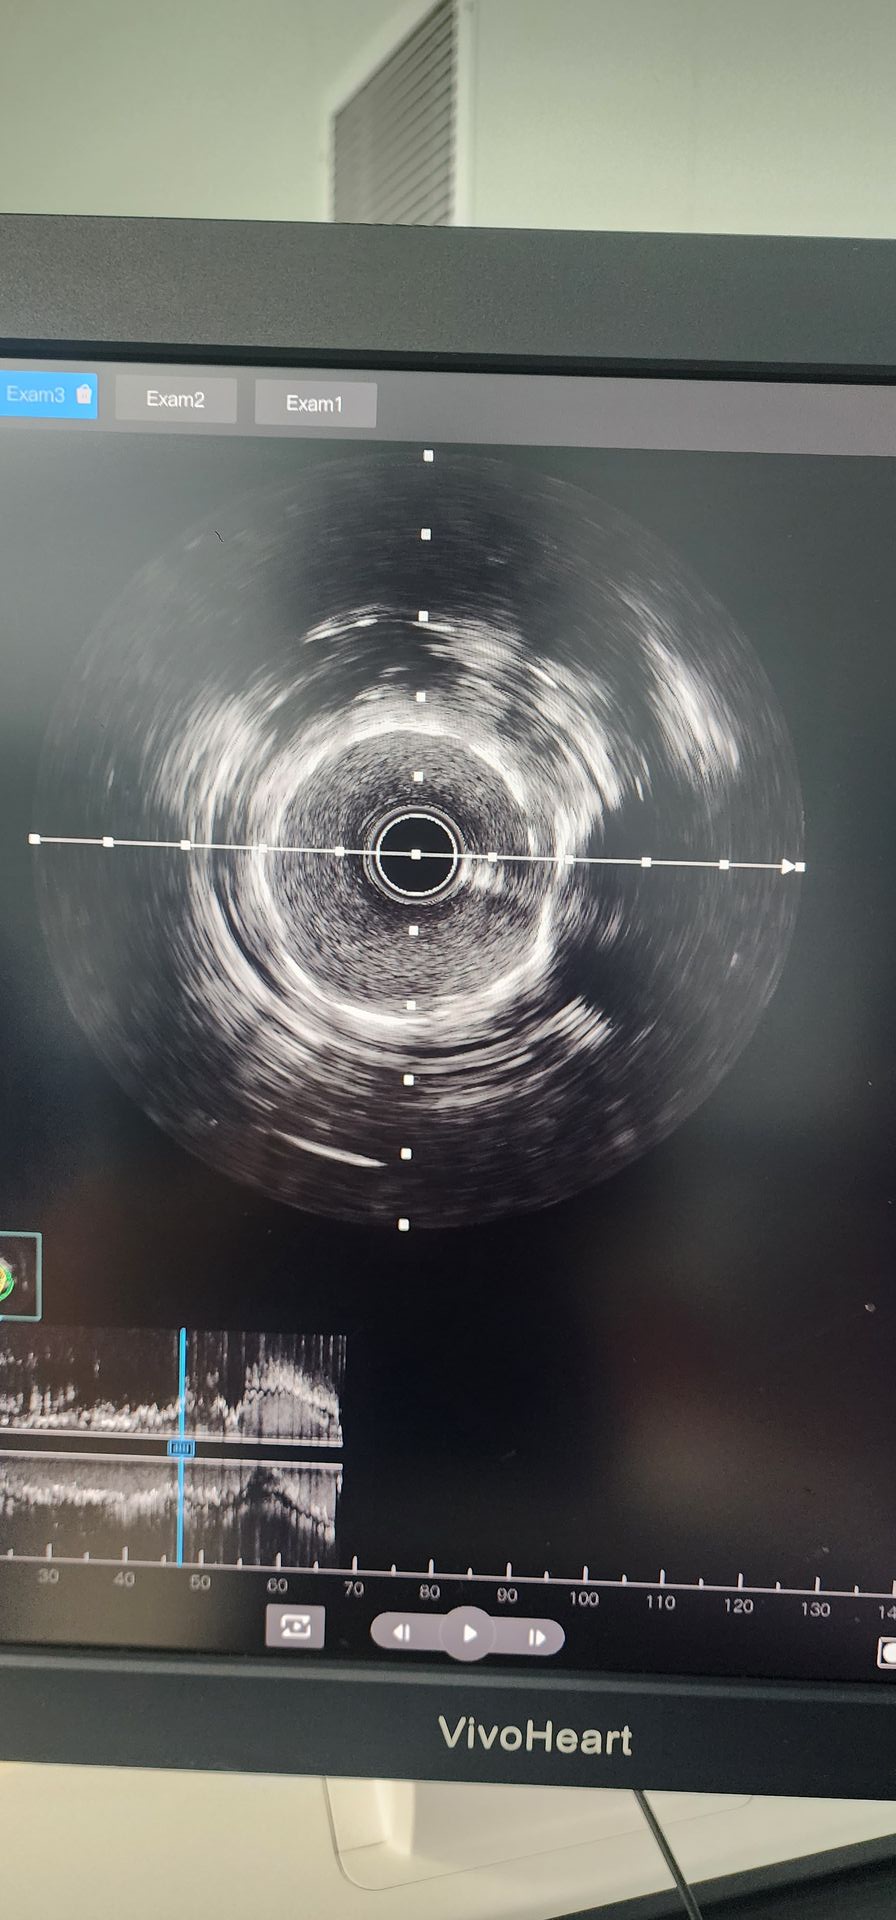

Angiografi koroner menunjukkan kalsikfikasi parah dengan 95% stenosis dalam proksimal pengobatan arteri dan 85%-90% kulasi stenosis dalam arteri koroner kanan menengah.

Proximal circflex Artery: awal pra-pelebaran dengan 2.0 × 20 balon menunjukkan hasil yang buruk. Sebuah 2.5 × 12 Lepu vesschcrack balon IVL koroner kateter kemudian digunakan, memberikan empat siklus, berhasil menebus lesi yang dikalsinasi. Setelah peningkatan signifikan pada stenosis, stent 2.5 × 14 berhasil ditanam, dengan hasil angiografi yang memuaskan.

Arteri koroner kanan tengah: awal pra-pelebaran dengan 2.5 × 20 balon yang dihasilkan dari peningkatan terbatas. Sebuah 2.5 × 12 Lepu vesschcrack balon IVL koroner kateter kemudian digunakan untuk dua siklus, secara signifikan meningkatkan stenosis dalam konstanta yang dikalsinasi. Stent 3.0 × 19 berhasil ditanam, hasil angiografi yang memuaskan.